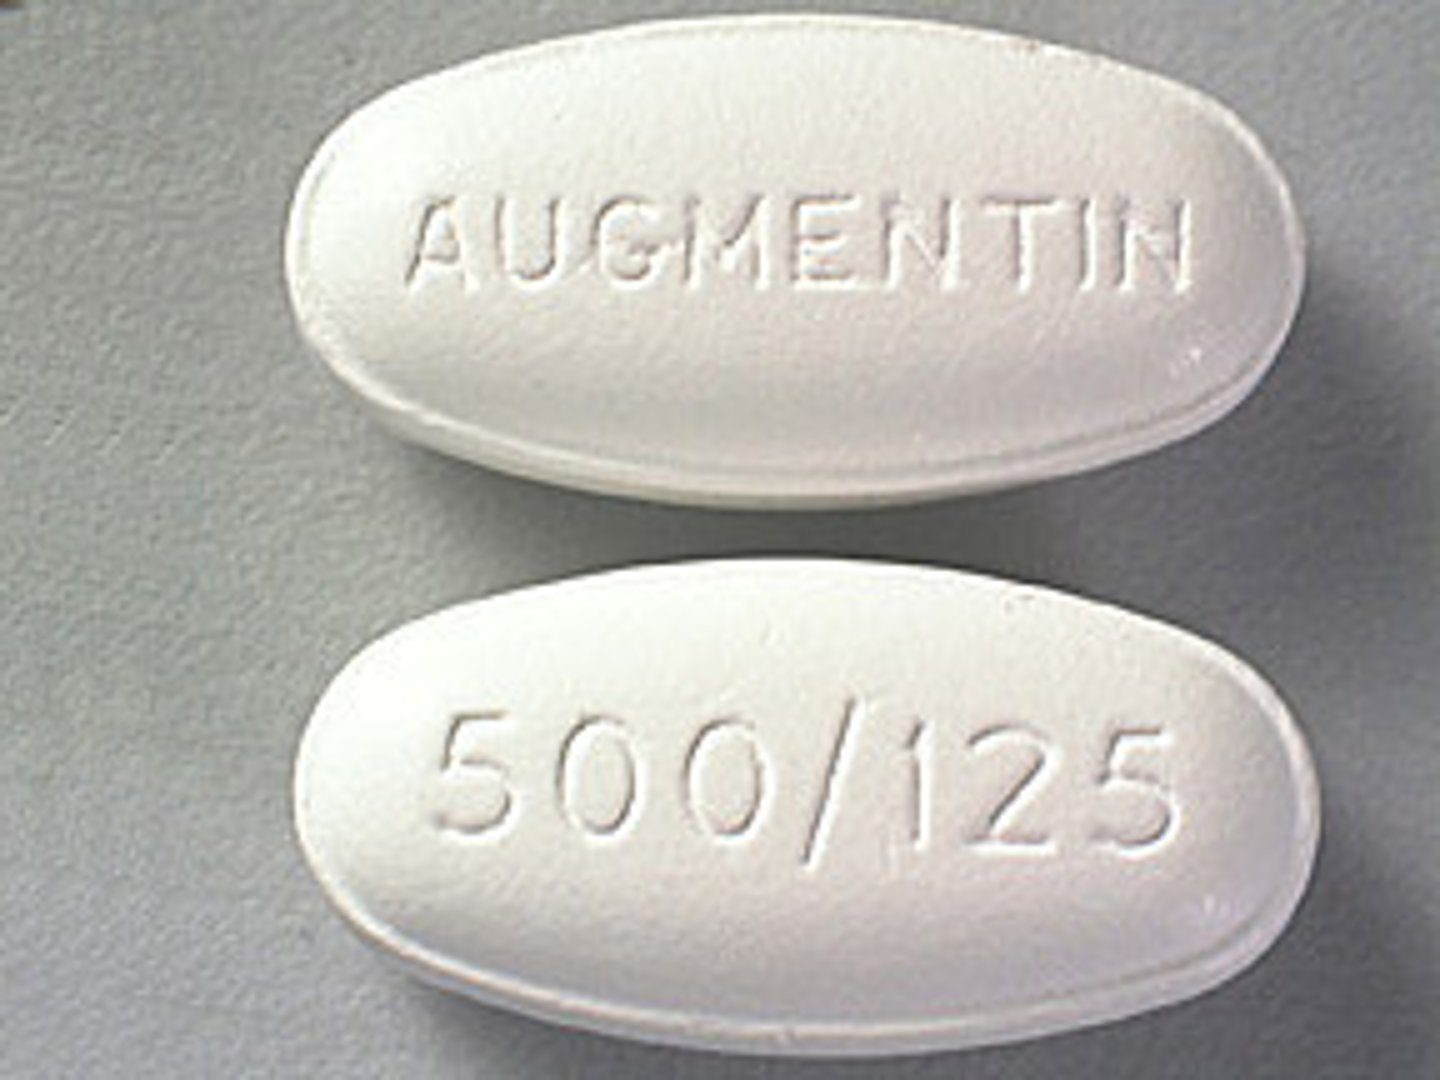

Amoxicillin

Brand: Amoxil

Class: Penicillin Antibiotic

Drug Interactions:

1) reduce effectiveness of birth control

2) Increased risk of bleeding with anticoagulants

Indication: Bacterial Infection

Schedule: NCLM